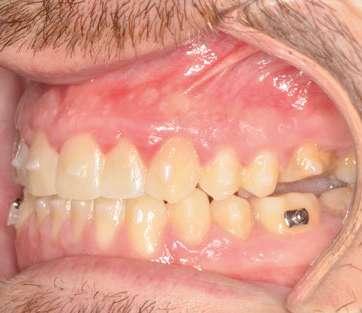

Fase 1: disyunción con MARPE

Tras colocar la anestesia palatina infiltrativa, el disyuntor osteo-soportado con tornillo hexagonal, se fijó de forma segura mediante los mini-tornillos utilizando un contra-ángulo de baja velocidad. Ese mismo día, se inició la expansión con pauta de 1 vuelta al día (0,16 mm por vuelta). Tras 43 días, se apreció la apertura de diastema inter-incisal y se continuó dando vueltas durante 18 días más hasta conseguir la corrección de la mordida cruzada posterior (Ilustración 5).

El paciente fue instruido en la higiene del dispositivo para evitar inflamación gingival y se realizaron controles rutinarios cada dos semanas. Al finalizar el procedimiento de expansión, el paciente fue monitoreado durante 75 días.

Evidencia clínica y radiográfica de la expansión:

 Separación visible de incisivos centrales, indicativa de apertura de la sutura palatina.

 Expansión confirmada mediante superposición de los modelos maxilares digitales previos y posteriores al tratamiento mediante MARPE (Ilustración 6). Se obtuvo un aumento transversal del 5,14 mm a nivel de los primeros molares.

Ilustración 5. Fotografías intraorales tras la disyunción con MARPE.